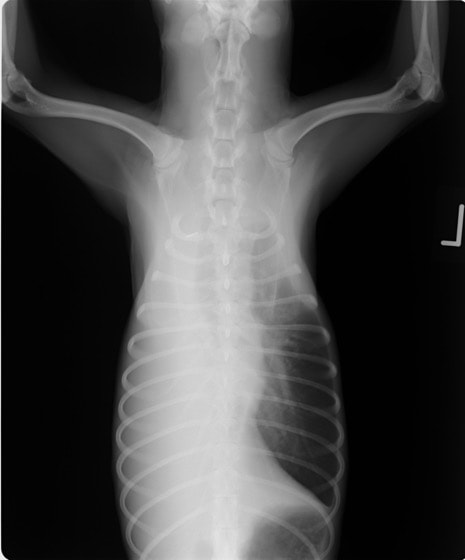

・ 胸部レントゲン検査:胸水貯留

・ 心エコー検査:異常なし

・ 胸水の性状:乳白色、TP:5.4g/dL、SG:1.038、TG:>500mg/dL、Tcho:65mg/dL、小リンパ球・好中球主体、細胞数:少ない

・ CT検査(リンパ管造影):無気肺以外の異常なし

レントゲン画像